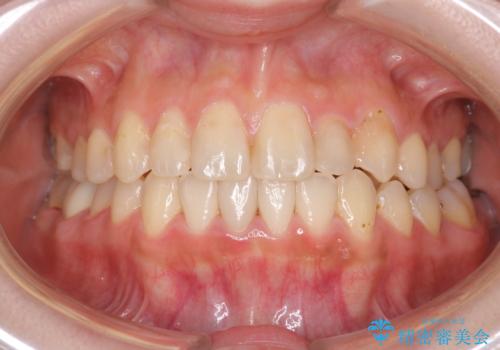

八重歯をインビザラインで非抜歯矯正

八重歯と前歯のガタガタがなくなり、歯並びがきれいになったのと、かみ合わせも改善することができました。